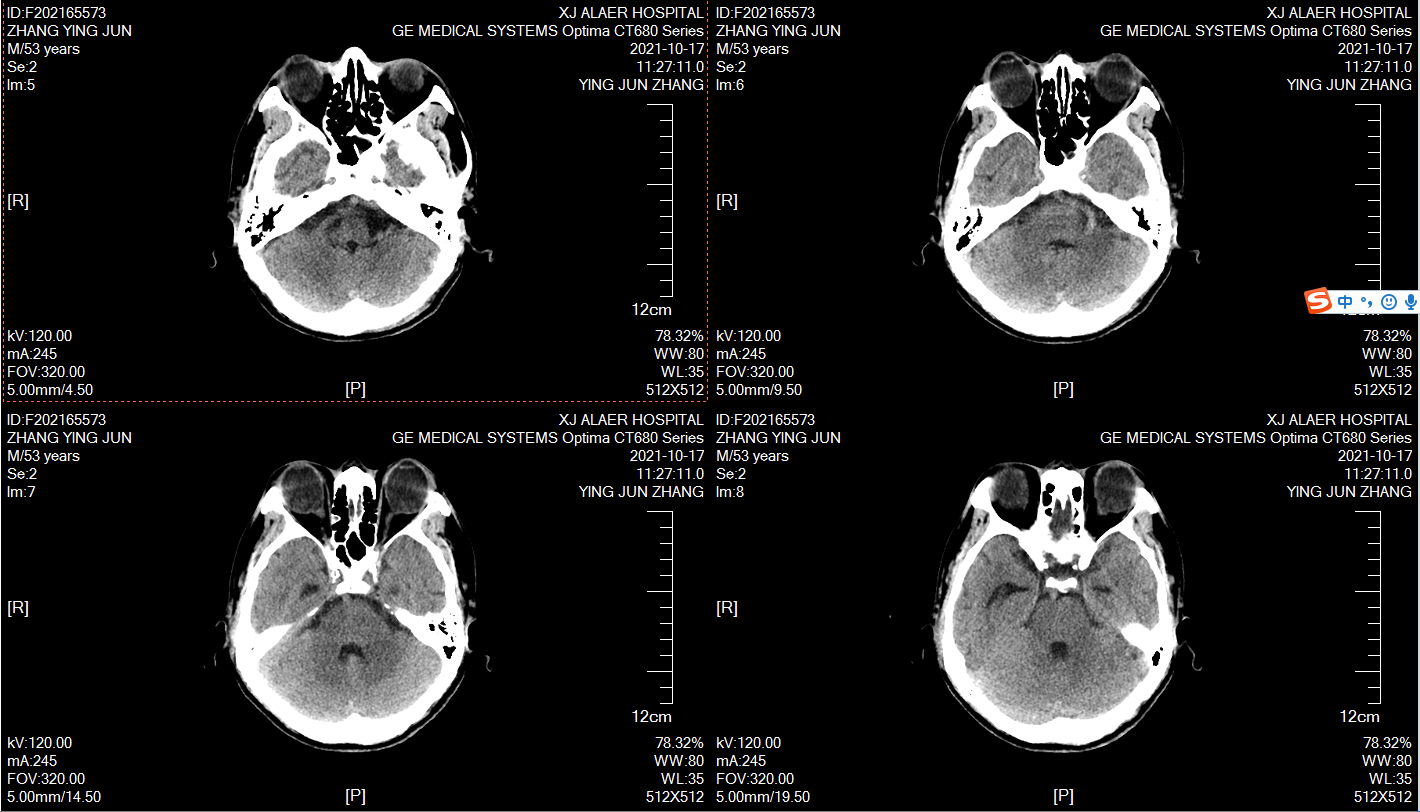

术后复查,尿激酶冲洗!

术后9天效果,夹闭24小时压力无明显变化,拔引流管!